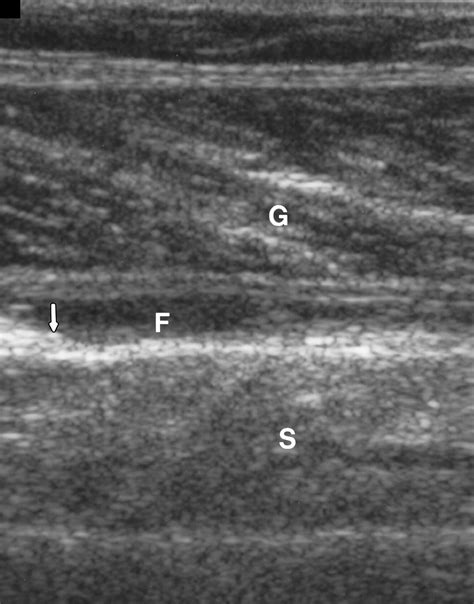

Calf muscle anatomy illustration

The calf is composed primarily of two major muscles: the gastrocnemius, which is the large, visible muscle that gives the calf its shape, and the soleus, which lies deeper underneath. Both of these muscles merge at the bottom to form the Achilles tendon, which attaches to the heel bone. When you push off the ground during walking, running, or jumping, these muscles work in harmony to plantarflex the foot (point the toes downward).

A tear in calf usually occurs when these muscles are stretched beyond their capacity during an eccentric contraction—when the muscle is lengthening while simultaneously trying to produce force. This frequently happens during sudden acceleration or a rapid change of direction.